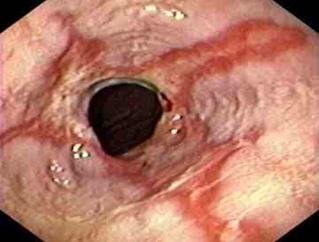

Figura 6. Esofagitis erosiva. Son visibles múltiples Figura 7. Esófago de Barret es una lesión premalgina. Metaplasia → displasia → adenocarcinoma (tercio inferior del esófago)

Terapia con IBP

♦ Considere si es asintomático.

♦ Continúe la terapia de mantenimiento a largo plazo si presenta síntomas. Endoscopia con biopsias de cuatro cuadrantes en cada 2 cm del área sospechosa (mucosa de color rojo salmón)

♦ Si no hay displasia: Repita la endoscopia cada 3-5 años.

♦ Si displasia de bajo grado: vigilancia cada 6-12 meses con biopsias cada 1 cm

♦ Si hay displasia de alto grado:

– Tratamiento endoscópico de las irregularidades de la mucosa (Ablación por radiofrecuencia, resección endoscópica) – Considere la cirugía: esofaguectomía con anastomosis termino – terminal.